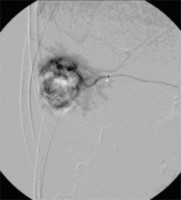

Superselektive transarterielle Chemoembolisation (TACE) mit Sondierung eines tumorversorgenden Gefäßes 1

(Bild 3 von 5)